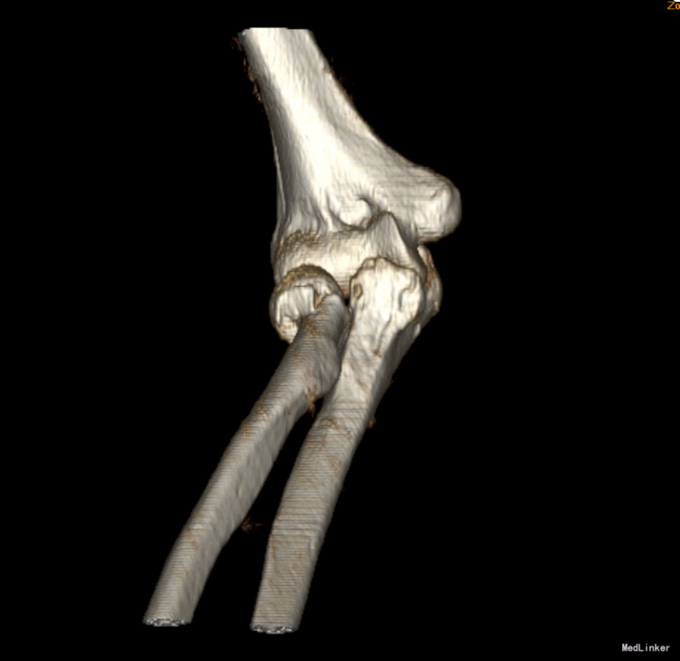

患者6小时前不慎摔倒,右手着地,当时即感右肘部剧烈疼痛,活动受限,被家人急送往奉天医院急诊,拍片检查示:右桡骨近端骨折,以“右桡骨骨折”收入院,现为进一步诊治,来我院就诊,以“右桡骨骨折”收入院,患者病来无头晕头痛,无恶心呕吐,无咳嗽咳痰,无发热寒战,饮食睡眠正常,二便正常,体重无明显减轻。

入院后完善检查,查无手术禁忌症后行右桡骨颈骨折切开复位内固定术,术后抗炎、接骨等对症治疗。术后第二天康复锻炼。术后2天一次换药,14天后出院。